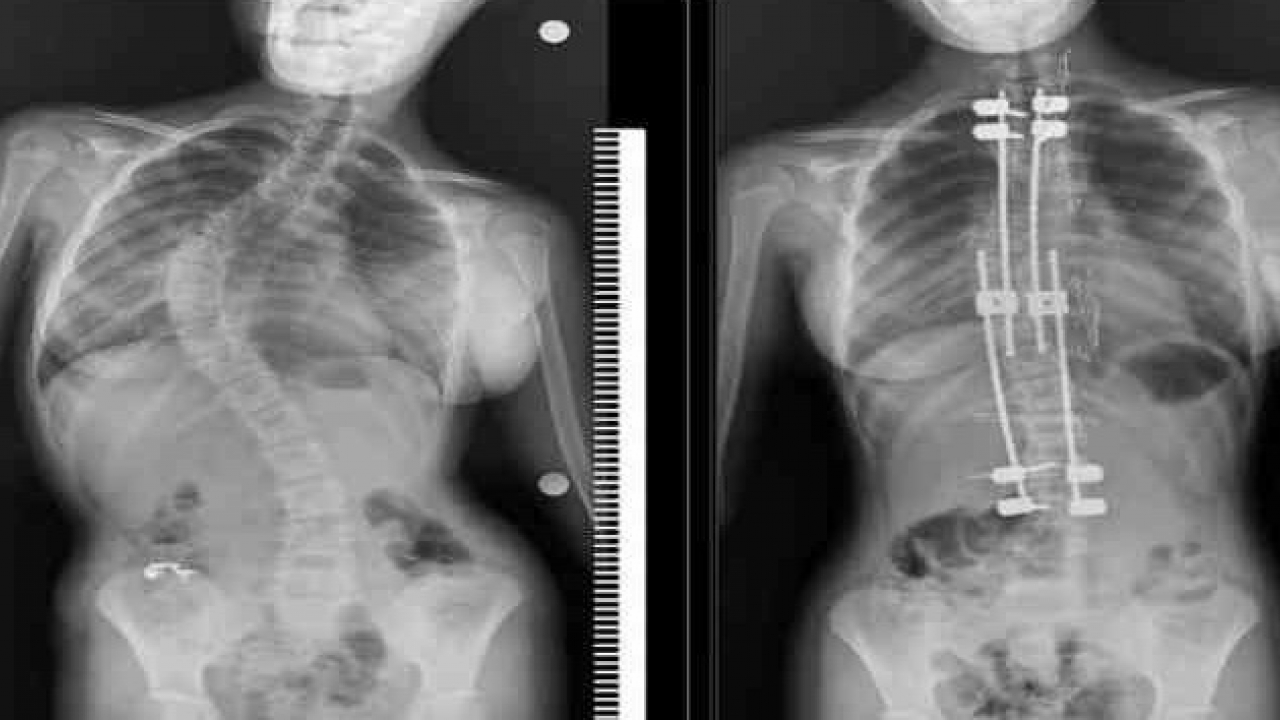

Skolyozlu çocuklar için doğru tedaviyle normal yaşam mümkün

Ortopedi ve Travmatoloji Uzmanı Doç. Dr. Hanifi Üçpunar, skolyozun doğal seyri, çocuklarda oluşturduğu etkiler ve tedavi seçeneklerine ilişkin önemli açıklamalarda bulundu. Skolyoz tanısının ailelerde ciddi tedirginliğe yol açtığını belirten Üçpunar, bu durumun sanıldığı kadar karamsar bir tablo oluşturmadığını vurgulayarak, “Skolyoz teşhisi konulan çocuklar hakkında ailelerin aklına ‘Hayat boyu ağrı mı çekecek?’, ‘İleride çalışabilir mi?’, ‘Kendi ailesini kurabilir mi?’ gibi pek çok soru geliyor. Oysa skolyoz, doğru yaklaşımla ve düzenli takiplerle yönetilebilen bir durumdur.” ifadelerini kullandı.

İleri derecede eğriliklerde cerrahinin bir seçenek olarak gündeme gelebileceğini söyleyen Üçpunar, ameliyat sonrası yaşamla ilgili endişelerin abartıldığını belirterek şunları kaydetti:

“Güncel bilimsel veriler, skolyoz cerrahisi geçiren çocukların yaşam kalitesinin sağlıklı yaşıtlarıyla neredeyse aynı olduğunu gösteriyor. Modern teknikler sayesinde bu hastalar eğitimlerine dönebiliyor, meslek sahibi olabiliyor ve sosyal yaşamda aktif yer alabiliyor. Cerrahi, bu sürecin sonu değil; pek çok çocuk için yeni bir başlangıçtır.”